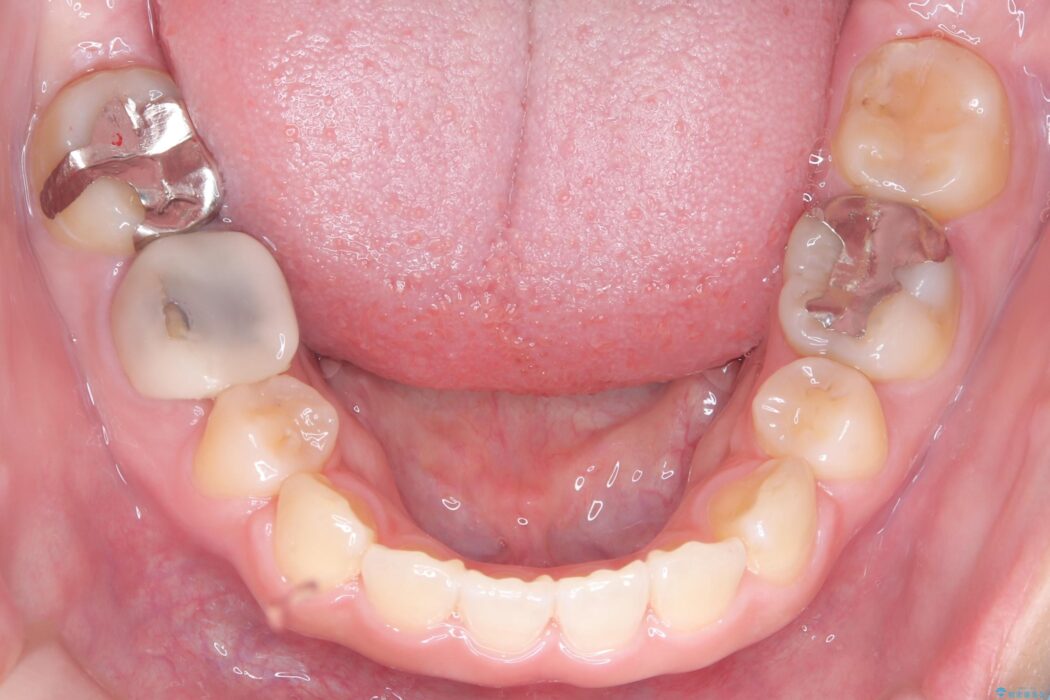

精密検査の結果、前歯を大きく後退させるスペースが必要と診断しました。

「前歯を下げたい」という患者様の強いご希望に応えるため、上下左右の第一小臼歯を抜歯。そのスペースを利用し前歯を奥へ移動させる治療計画を立案しました。

今回の矯正治療では、前歯を大きく後退させるスペースを確保するため、計画通り上下左右の第一小臼歯を抜歯しました。

装置には、上顎には目立たない裏側矯正(舌側矯正)を、下顎には透明な審美ブラケットを使用するハーフリンガル矯正を採用しました。抜歯によってできたスペースを最大限に活用し、前歯を効率よく後方へ移動。治療の結果、口元の突出感が大幅に解消され、Eライン(横顔の美しさの基準)も改善しました。人目を気にすることなく治療を完遂し、自信の持てる美しい横顔を獲得していただけました。